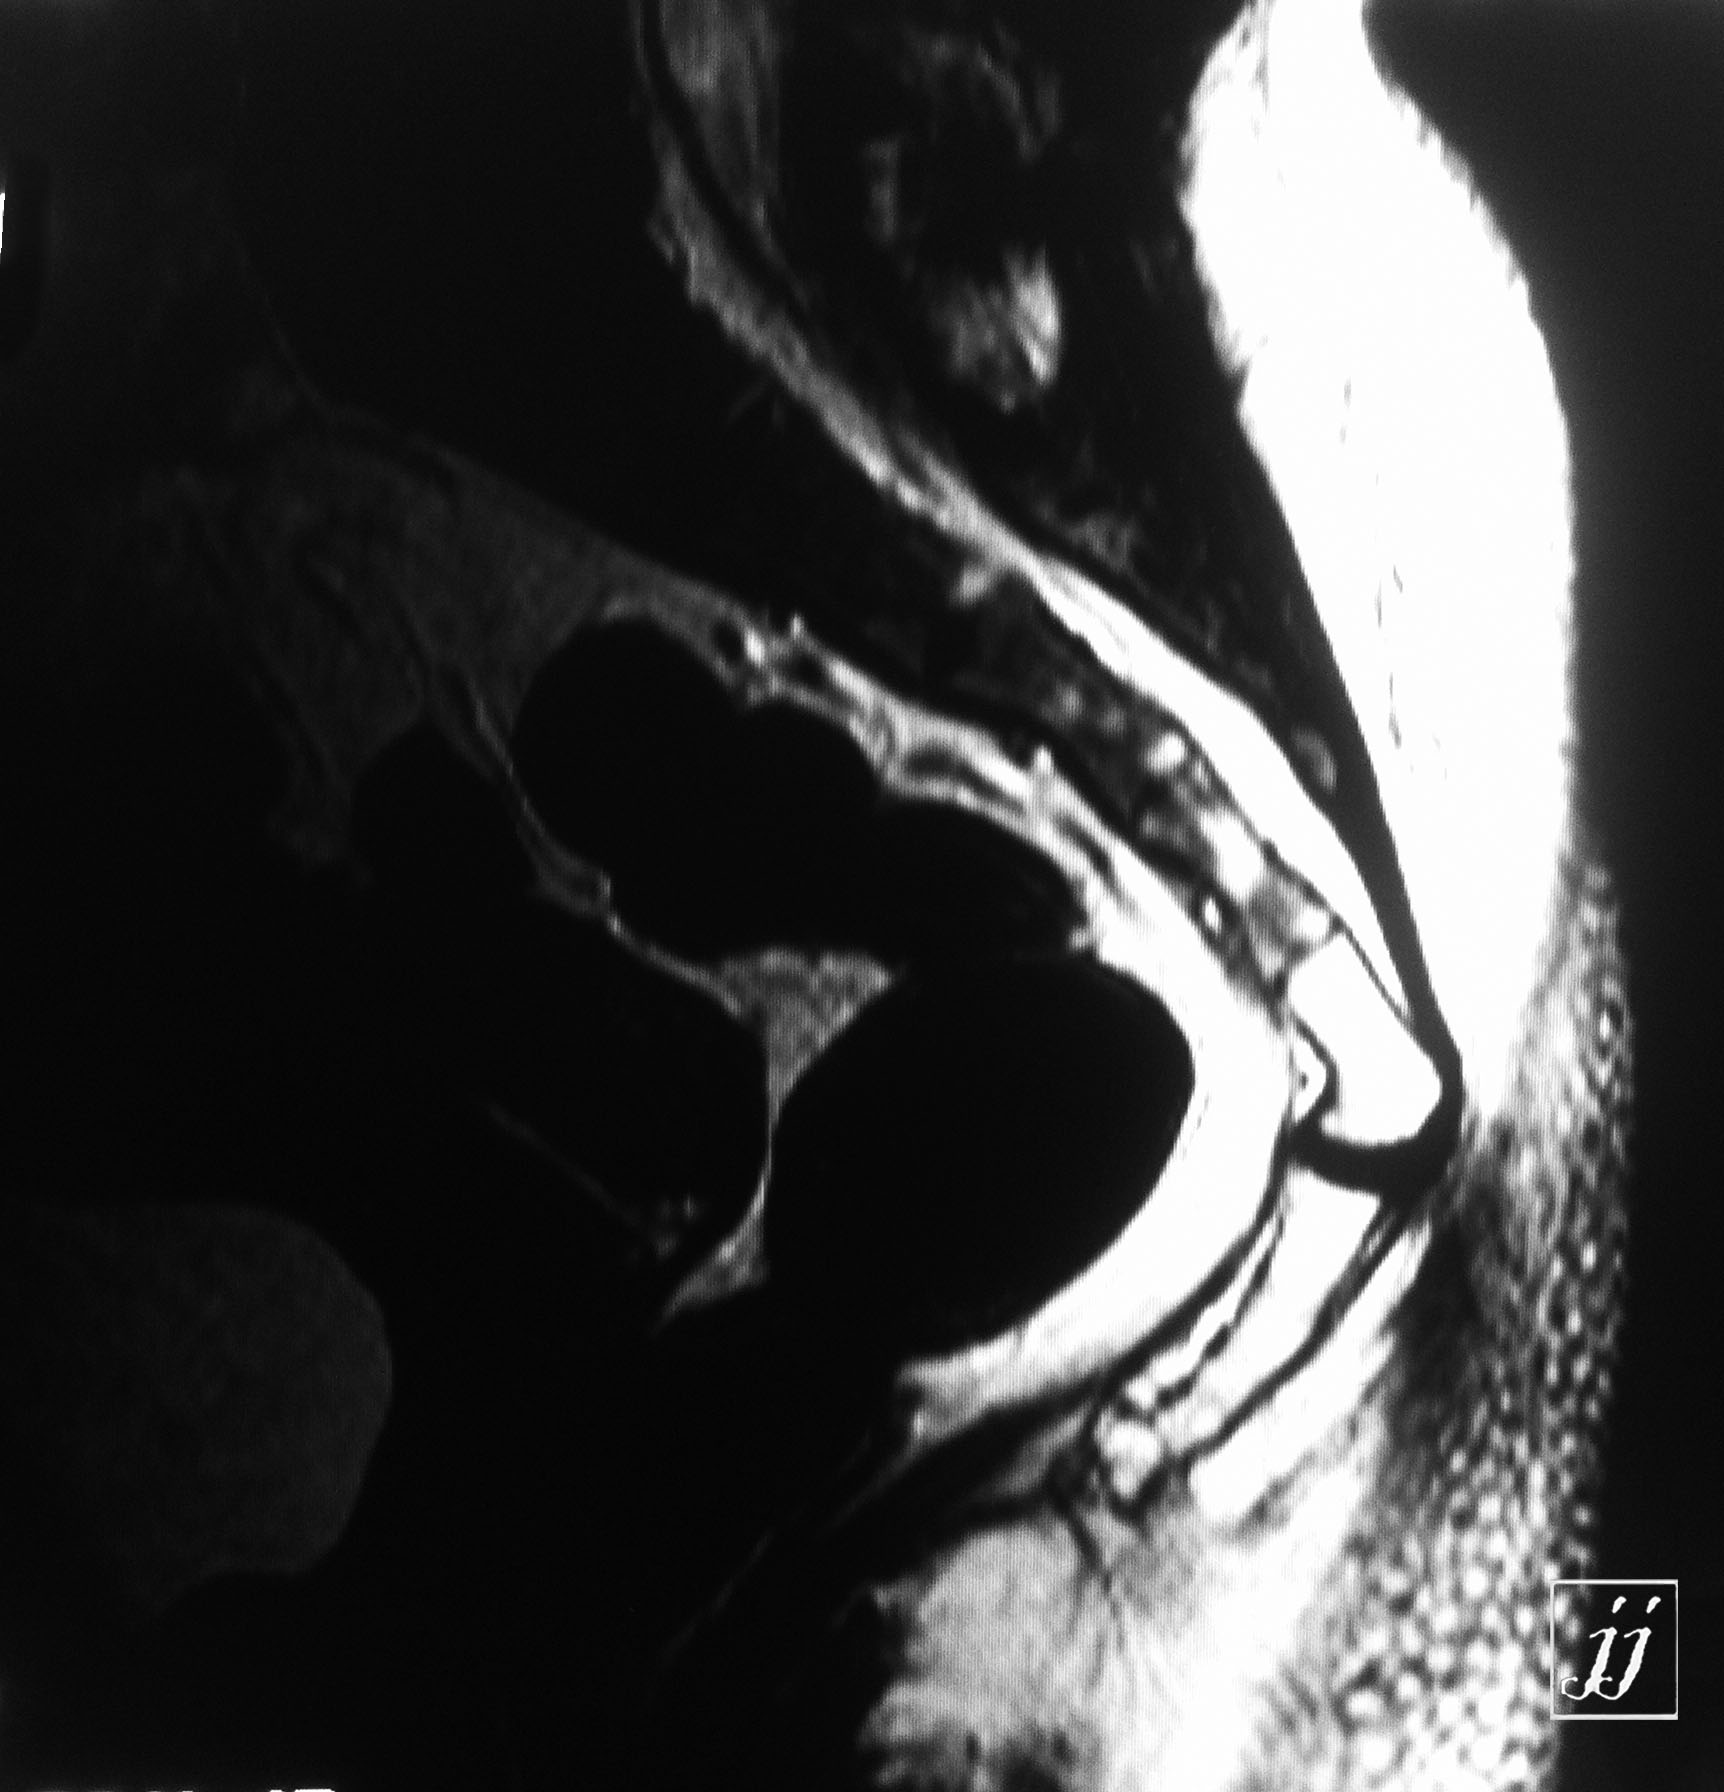

MSK- distal femur lesion that operated before (9)